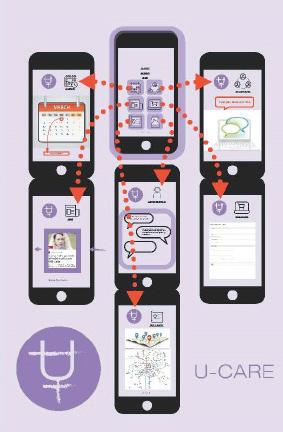

U-CARE is an organization aiming to open access of medical treatments and prescriptions concerning reproductive health, especially contraceptives, as well as medications for transgender people, due to the concerning difficulties for transgender people to receive proper and on-time medical treatments, as well as long-term discriminations and lack of systematic supports from the every other sectors.

U-CARE works in two forms, one as a semi - public booth that has a similar working mechanism as vending machines while also provides individual space to get in touch with doctors and care providers, or to deal with any issues that needs urgent private and safe space, to avoid awkwardness.

Another is an online platform, an app that helps users to quickly browse the nearest booth around. Users can permit the system to collect certain in order to receive more customized services including prescription reminder, network linking to people with same issues, or resources that help with legal and health issues, etc.

The goal is to build an organization that addresses the issues of the lacking of sufficient medical support for transgender people, sets up a network that links supply for regular medications and forms an online community, offering a safe and adequate supporting system.

Anyone can freely access the booth, but if the user wants their treatment histories be recorded, several ways are available, either enter the booth by inputting fingerprints, type in username, or scan QR code through the app.

By entering the booth, people can go to the sink to wash their hands or directly work on the touch screen to receive services, which mainly include, purchasing regular medicines and prescriptions or talking to a doctor or care provider in this private space. A skylight is opened up, but covered with colored glass to keep certain privacy, the radial structure influences the interior material choices. Tiling expresses like strips, the various materials also functions to differenriate between programs.

Browsing Services

Picking Up Prescriptions

Taking a moment to appreciate yourself

Remote Diagnosing